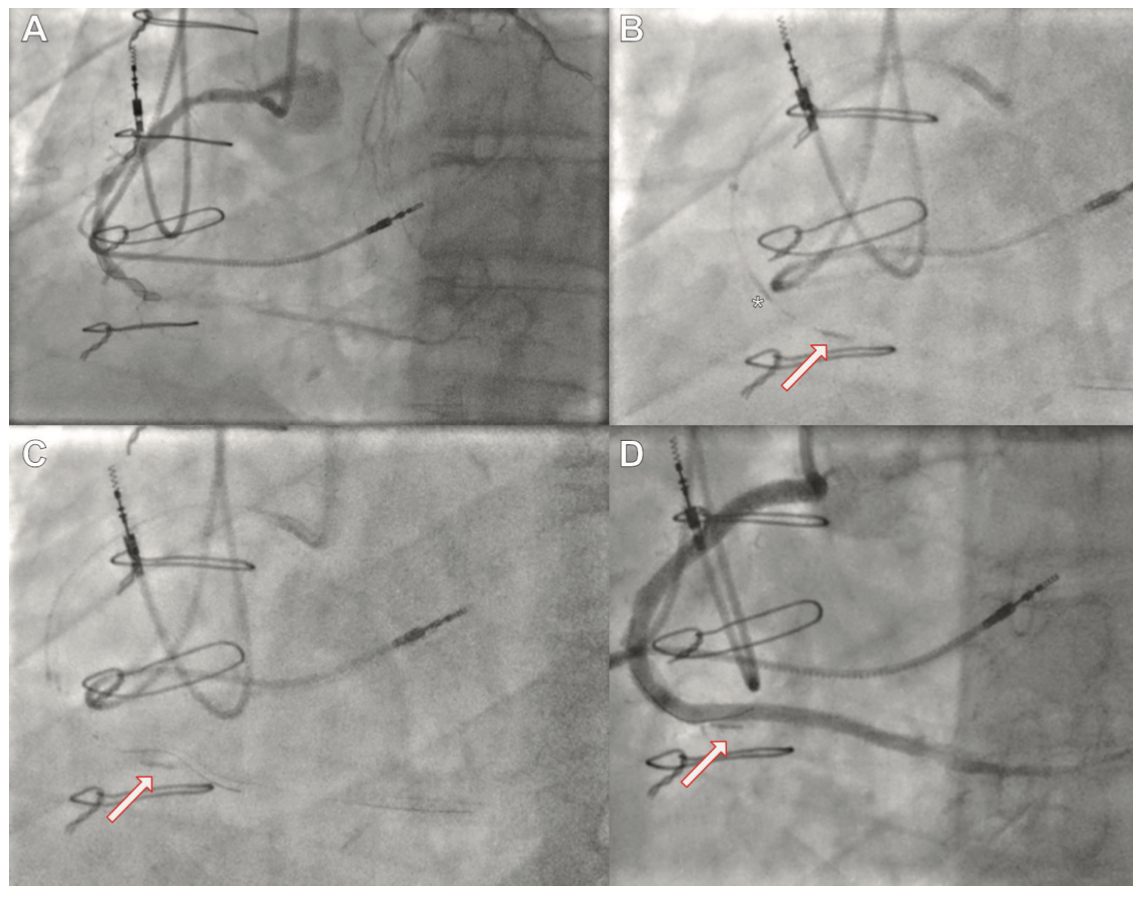

Case 2. An 82-year-old male with CCS 3 angina due to triple-vessel disease and, specifically, an occlusion in the mid LAD artery (J-CTO score 3) (Figure 2A) was treated with PCI consisting of biradial 7-Fr access, Extra-Backup (EBU) 3.5 to the left coronary artery and AL1 to the RCA with an initial AWE approach using a Turnpike Spiral microcatheter and a Gladius Mongo wire. We were able to cross the mid LAD lesion, but were subsequently unable to advance or rotate the microcatheter with modest amount of force due to angulation and heavy calcification. The microcatheter tip disintegrated and remained dislodged in the CTO segment (Figure 2B). Brief attempts to re-cross in distal true lumen using Gaia third wire (Asahi Intecc) and Confianza Pro 12 wire failed, as did an ADR attempt using a Gladius Mongo wire only. Employing a side-BASE technique using a 3.0 balloon in the D1 branch allowed us to advance a Pilot 200 wire in the subintimal space proximal to the occlusion and a second Turnpike spiral MC successfully tracked around the occlusion (Figure 2C). We completed an ADR using a Stingray balloon and Hornet 14 wire using the stick and drive technique. Using IVUS for sizing, the distal to proximal vessel was predilated and subsequently stented with overlapping drug-eluting stents. Following stent deployment, the patient developed hypotension due to a proximal LAD perforation causing a pericardial effusion; this was treated with a 3.5 x 20-mm covered stent and pericardiocentesis, restoring normal hemodynamic parameters with a good angiographic result (Figure 2D). Again, using a dissection re-entry technique, the retained microcatheter tip was effectively jailed behind stent struts within the vessel architecture.